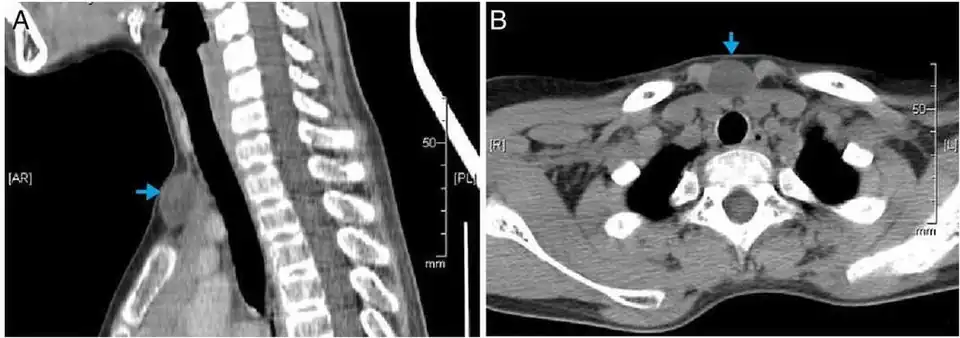

Epidermoid cysts are usually diagnosed when a person notices a bump on their skin and seeks medical attention. The definitive diagnosis is made after excision by a pathologist based on microscopic appearance of a cystic lesion lined by cornified epithelium containing lamellated keratin without calcifications. They can also be seen as isointense lesions on MRI or hyperintensities on FLAIR.

In case of fronto-ethmoidal epidermoid cysts, surgical resection appears to be the mainstay of treatment; however, the extent of resection is dictated by adherence of the tumor capsule to the surrounding vital structures.[7]